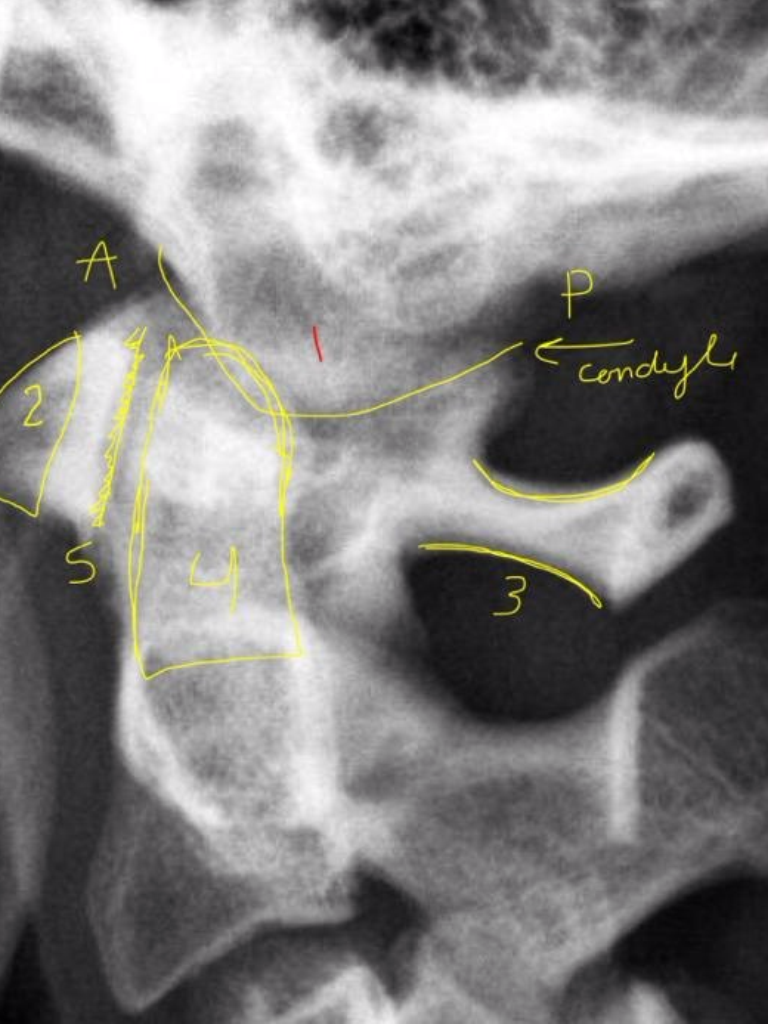

14

Q

1

A

Occipital Condyle

(anterior/posterior)

15

2

Anterior Tubercle C1

16

3

Posterior Arch C1

17

4

Odontoid Process C2

18

5

Atlanto-Dental Interspace